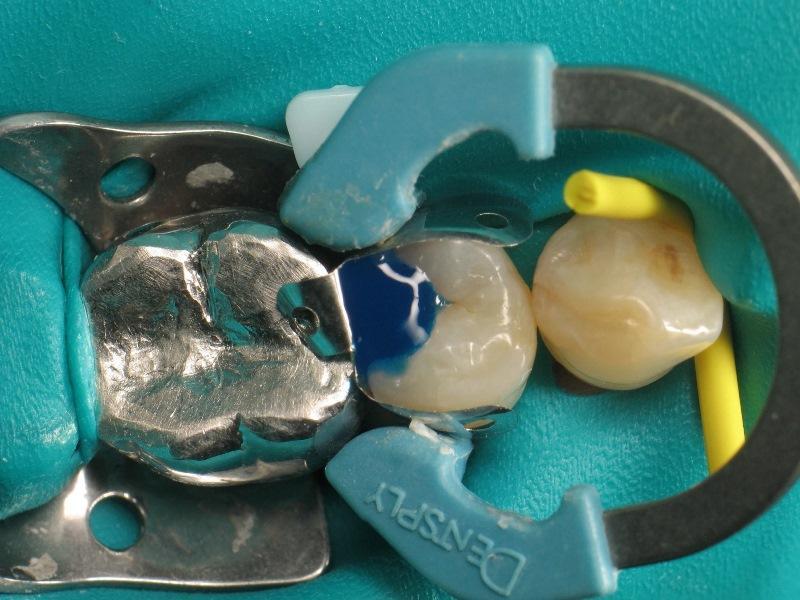

Фото 4: Установка проксимальной матрицы.

Для достижения удовлетворительной анатомии и функциональности необходимо учитывать несколько элементов: препарирование, разделение межзубных промежутков и контурная пластика. Для восстановления проксимальной стенки, разрушенной кариозным поражением, следует использовать матрицу. Как правило, используется металлическая матрица, поскольку она податлива и не прилипает к реставрационному материалу. Высота матрицы имеет решающее значение. Если она будет слишком короткой, пломба будет нарушена, а если она будет слишком длинной, манипуляции будут затруднены из-за десневого сосочка. Разделение межзубных промежутков включает в себя расширение межзубного пространства с помощью клина. Обычно клин изготавливается из дерева или пластика различных размеров. Размер клина имеет решающее значение. Если клин слишком мал, точка контакта будет слишком свободной, но, если клин слишком большой, может возникнуть послеоперационный дискомфорт. Контурная пластика включает в себя определение общей формы проксимальной поверхности зуба. Чтобы прижать матрицу к зубу и придать реставрации естественную форму обычно используется кольцо.